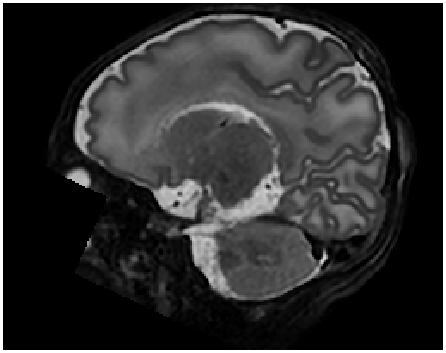

Refer to caption

Figure 8: Qualitative comparison between cubic B-spline and proposed method for upsampled cardiac short-axis stacks (ACDC dataset). Volumes were upsampled with factor 101010 from 101010mm (original) to 111mm slice spacing. Shown are sagittal views through upsampled short-axis stacks. The proposed method can generate new slices that result in smoother anatomical transitions compared to slices generated by conventional interpolation method. The performance difference is more pronounced for the structures of the left ventricle myocardium. Note that a feature located at the apex of the right ventricle seems to appear more accurate in the upsampled image using cubic B-spline interpolation method compared to the proposed approach.